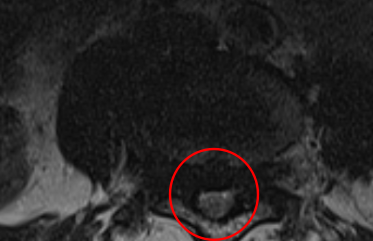

治療後

術後の翌日には痺れが軽減。術後2週間程度で痛みは10から0に、左下肢疼痛は10から1に緩和しました。また術後のMRIでも狭窄症の圧迫がきれいにとれていました。